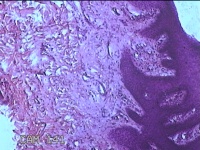

右侧足底结节

性别

男

年龄

41岁

临床诊断

鸡眼和胼胝

一般病史

发现右侧足底结节伴隐痛不适半年余。

标本名称

大体所见

灰白粉红色带皮肤样结节1x0.8x0.3cm一个,表面糜烂,切开结节呈实性,切面灰白粉红色,质硬。

图2